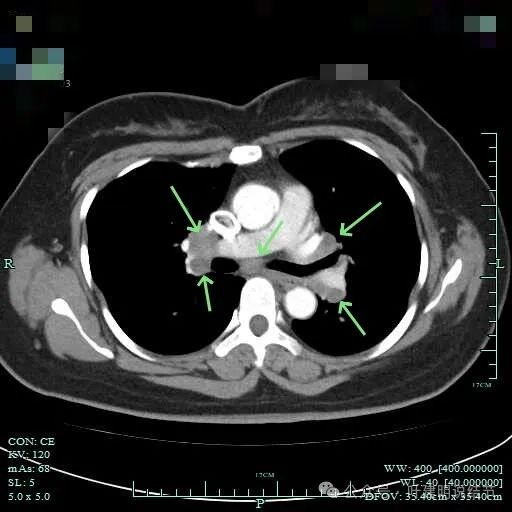

双侧肺门与纵隔明显肿大淋巴结。

左侧肺门与纵隔肿大淋巴结

左侧肺门处淋巴结肿大明显。

右侧腔静脉旁肿大淋巴结。

右侧肺门与纵隔肿大淋巴结